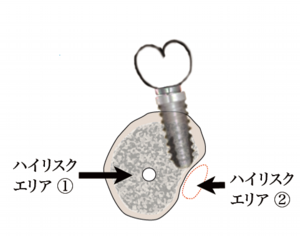

インプラントの噛み合わせの重要性が見直され、きちんとした噛み合わせが大事ということが証明されたのち、かぶせの歯の位置を決めた後にインプラントをいれるという順序にかわりました。しかしこの治療はCTが必ず必要となり、また経験が必要とされる骨造成も必要になることが多く、絵のようにハイリスクエリアに近接してしまうこともありますので、トラブルもやはり存在しています。

ガイドを用いたインプラントの埋入が世界的スタンダードになりつつあります。そのため当院でも上顎前歯のような審美領域や下顎臼歯など解剖学的危険エリア。またその他既存骨などの少ない骨を利用したケースでは採用をほぼ義務付けさせて頂きます。これらについて詳しくはCTによる診断が必要ですのでCTによる撮影後、必要かどうかをお伝えします。